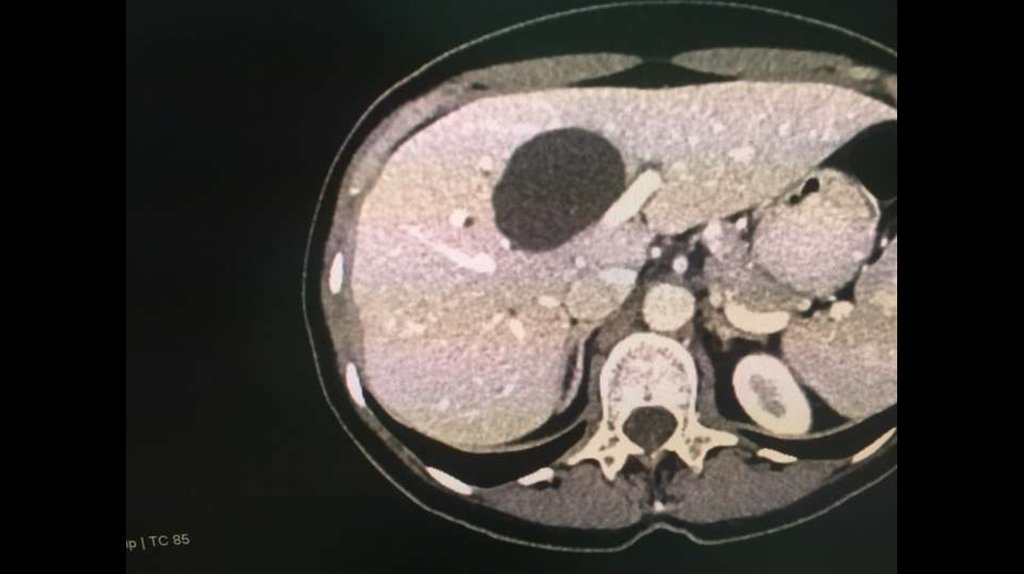

По направлению из ЦГБ в ККБ №1 поступил пациент М., 48 лет, с диагнозом «Эхинококкоз

печени»

Пациенту в плановом порядке выполнено КТ ОБП. По результатам исследования выявлена

эхинококковая киста IV-V сегментов.